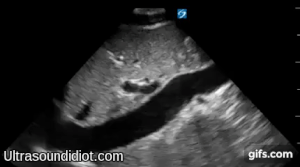

Echo Subcostal Exams